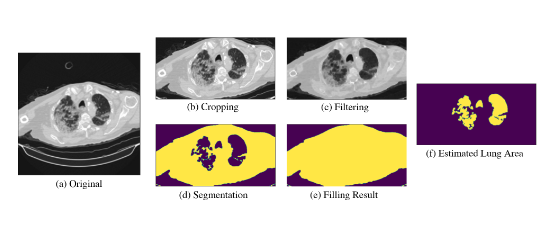

论文针对 CT 扫描图像分辨率和切片数量不一致问题,提出基于两步法的模型。先通过肺面积估计选择切片训练 2D 模型,再用 LSTM 和 Swin Transformer 学习时空特征,实验证明该方法有效。

创新点:

1.提出基于肺面积估计的切片选择策略,提升训练数据质量。

2.构建结合 LSTM 和 Transformer 的两步法模型,学习时空特征,避免过拟合。

3.发现两步法中 LSTM 模型假阴性率低,Swin 模型假阳性率低,为模型集成提供依据。